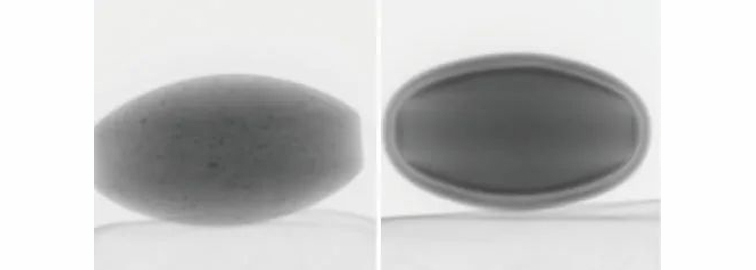

图2 样品照片:左边片剂A,右边片剂B

在本例中,观察到两种具有不同结构的片剂(片剂A和B)(图2)。片剂的透视图像如图3所示。

片剂A (左) 片剂B(右)

图3 片剂透视图